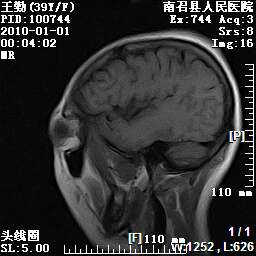

以下是引用随光逐影在2010-1-22 9:03:00的发言:[br]考虑左侧中颅窝(蝶骨翼区)脑膜瘤侵犯蝶骨翼并突入左侧眼眶。

以下是引用水过无痕在2010-1-22 14:55:00的发言:[br]一、定位:颅外占位;二、定性:恶性可能性大;三、组织来源:来源于左侧眼外直肌或其他部位;考虑为:横纹肌肉瘤>转移瘤>脑膜瘤.